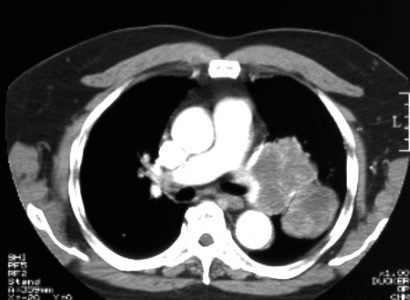

Παραδείγματα πότε μπορεί να βοηθήσει η εξέταση (ΕBUS) στη διάγνωση